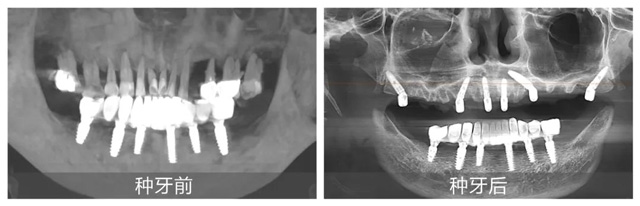

在配备数字化导板系统的现代化手术室里,黄杰终于迎来期盼已久的“试炼场”。短短一年,就已经成功种植修复2100+颗牙,完成无牙颌即刻负重手术110台。不仅在种牙数量上取得了突破,在质量方面也同样出色。

日前,黄杰为一位种牙顾客实施“即拔即种”手术,从拔除残根到植入种植体仅用15分钟,创面控制得如同经过精密计算一般。但让他最有成就感的,还是那些从牙槽外科延续而来的“全流程治疗”:曾有位患者因埋伏多生牙导致囊肿,他先微创拔除患牙,待运用颌面外科的骨移植修复骨缺损后又为其完成种植修复。“能看到顾客从治疗到重获咀嚼功能的完整过程,这是口腔医生特有的幸福。”